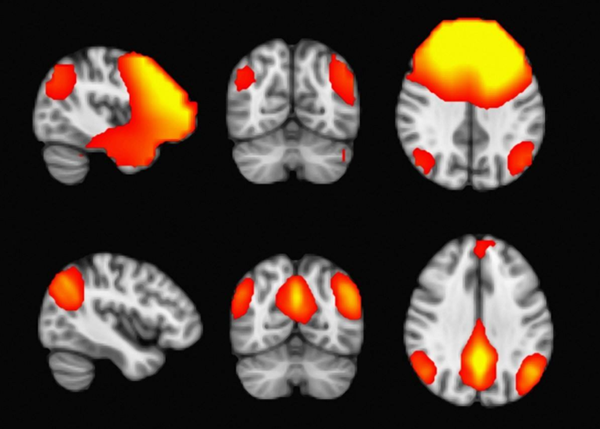

我们在加拿大多伦多大学儿童医院(SickKids)引入了脑磁图(MEG)指导的难治性局灶性癫痫儿童癫痫手术。顽固性局灶性癫痫患儿的手术候选资格和手术程序的决定基于长期头皮视频EEG(VEEG)结果,磁共振成像(MRI)发现,以及MEG尖峰源的分布。在癫痫发作会议上进行了多学科讨论后,对于需要颅内VEEG的患者,使用三维MRI与MEG尖峰源叠加设计定制的硬脑膜硬膜下电较网格,以覆盖成簇的MEG尖峰源区域。在一开始手术中,神经外科医师使用术中神经导航系统可视化MEG上成簇的棘突偶较子和体感诱发场的区域,以放置硬膜下网格和深度电较。在二次手术中,切除颅内VEEG记录中的发作发作和活动性发作间壁尖峰放电的区域,该区域通常与成簇的MEG尖峰源区域相关。这种结合导致成功的手术结果,以控制这些具有挑战性的小儿患者的癫痫发作。MEG是顽固性局灶性癫痫患儿确定手术候选者和局灶性皮质切除以阻止癫痫发作的有用工具。

此外,磁性脑磁图(MEG)的临床测量可以超导量子干涉装置来记录颅内神经元活动的小磁场,电流的流动需平行与颅骨的表面,以便通过MEG传感器产生和检测垂直磁场为临床治疗提供指引和方向。

使用MEG在小儿癫痫发作期和发作间期视频脑电图的组合来协助致癫痫区的定位,结果之间的一致性提供了强有力的非侵入性证据,这是手术成功的确定。